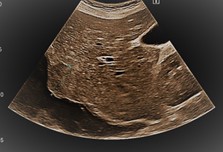

Leber

Darstellung und Identifikation im B-Bild

Diffuse Leberveränderungen

Anatomie und Normalbefund an: Leber, Gallenblase, Pankreas, Nieren, Milz, Retroperitoneum, Unterbauch - häufige Befunde und Ausblick auf die häufigsten Differentialdiagnosen.